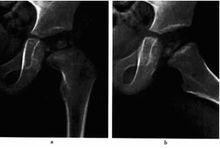

雙側股骨頭骨骺缺血性壞死(進展期)圖9-4雙側股骨頭骨骺缺血性壞死(進展期)

a.b 平片,示雙側股骨頭骨骺變扁.密度增商.其中右側頭骺及左側乾骺端夾雜囊變透亮區